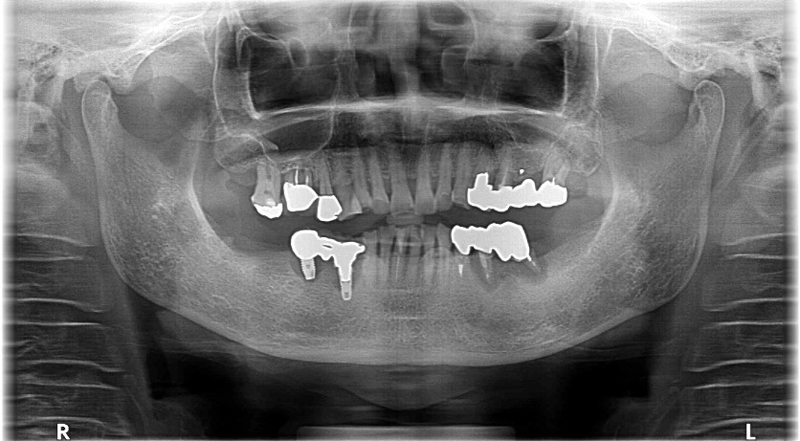

他医院でインプラント治療を行ったが、治療後に「インプラントがグラグラする。」「インプラントが痛い。」などの症状を発症。「インプラントは問題なく埋まっている。咬合調整をすれば症状は改善する。」と言われ、数か月間通院したが一向に改善しなかった。そこで、クリニック長が日本口腔インプラント学会専門医である当院にセカンドオピニオンで来院。

こちらは、先述のセカンドオピニオン来院時のレントゲン写真を拡大した写真です。